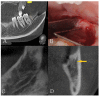

The purpose of this observational study is to evaluate the prevalence and main characteristics of bifid canals within a European adult population, analyzing cone-beam-computed tomography (CBCT). The population study examined 300 subjects. The CBCTs were performed between 2012 and 2019, using PaX-Zenith3D with a standard protocol of acquisition. The parameters analyzed were the presence and lengths of the bifid mandibular canals. The sample included 49% male and 51% female participants. The mean age of the patients was 47.07 ± 17.7 years. Anatomical variants of the mandibular canal were identified in 28.8% of the sides and 50.3% of the patients. In 7.3% of the subjects, the anatomical variants were present bilaterally. The most frequently encountered bifid canal was Type 3 (40.5%), followed by the Type 1 canal (39.3%), the Type 2 canal (14.5%), and the Type 4 canal (5.9%), 40% on the right side and 60% on the left side. The average length of the bifid canals located on the right side of the mandible was 11.96 ± 5.57 mm, compared to 11.38 ± 4.89 mm for those measured on the left side. The bifid mandibular canal is a common anatomical variation of the mandibular canal. It is fundamental to performing an accurate preoperative evaluation using CBCT analysis to avoid and/or reduce intraoperative and postoperative complications.